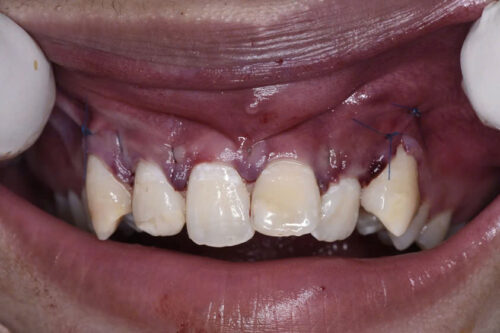

Trong nha khoa, các trường hợp răng thừa ngầm, đặc biệt là ở vùng cửa, là vấn đề không hiếm gặp. Răng thừa ngầm là những chiếc răng không hoàn chỉnh, mọc lệch, hoặc nằm dưới nướu mà không thể tự trồi lên bề mặt. Các răng này có thể gây ra nhiều vấn đề cho bệnh nhân như viêm nhiễm, nhiễm trùng, hoặc ảnh hưởng đến quá trình mọc của các răng khác. Phẫu thuật lấy răng thừa ngầm vùng cửa là một phương pháp điều trị phổ biến để giải quyết tình trạng này. Bài viết này sẽ trình bày chi tiết về quy trình, lý do, và các yếu tố cần lưu ý khi thực hiện phẫu thuật lấy răng thừa ngầm.

Các răng thừa ngầm thường gặp ở vùng cửa (răng cửa), là những chiếc răng nằm gần với mặt trước của hàm, và có thể gây ra nhiều vấn đề như sự không đều trong cung hàm hoặc cản trở sự phát triển của các răng khác.